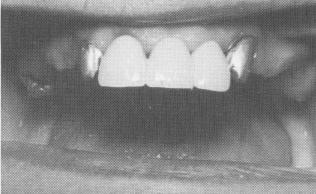

Fig. 10-173. The anterior quadrant is secured to the abutment teeth with oxyphosphate of zinc cement.

1 Maxillary anterior quadrant secured to abutment teeth with zinc cement